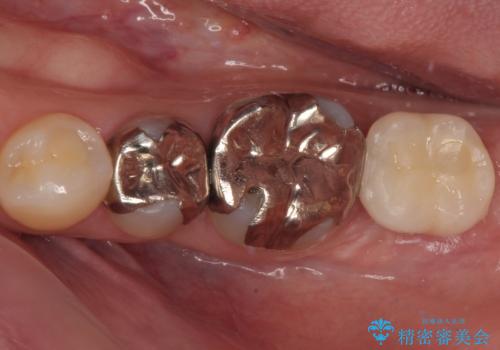

奥歯が取れた フルジルコニアクラウン

担当医 小澤俊哉